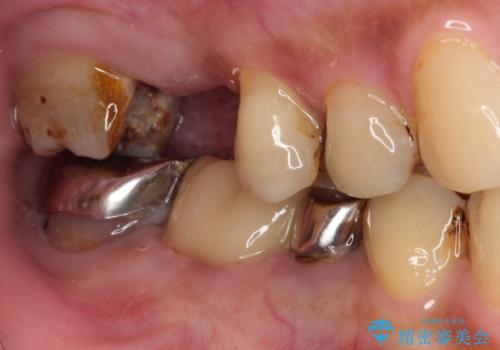

- 詰め物が外れたまま放置してしまったとのことで来院された患者様です。

詰め物が外れた部分は虫歯が進行しており、周辺には歯石が付着している状態でした。

1歯欠損していたため、オールセラミックブリッジによる補綴治療を行うこととしました。